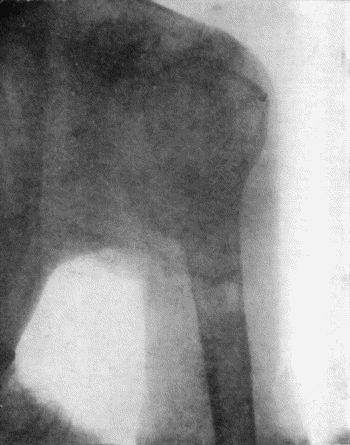

189 50.Chondroma growing from Infra-Spinous Fossa of Scapula

190 51.Chondroma of Metacarpal Bone of Thumb

488 143.Skiagram of Multiple Chondromas

489144.

Multiple Chondromas in Hand